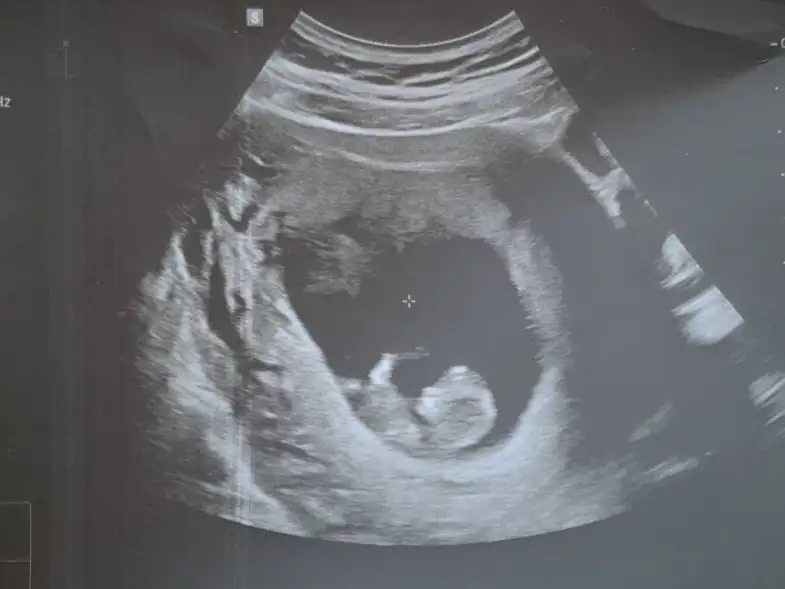

Bizi de yorumlayan biri olabilir mi şuan 12+3 ama fotoğrafta 11 haftalık doktor bir benzetmede bulundu ama net olmadığı için sevinemiyorum 😇

Eklentiler

• 20230216_125345.webp

20230216_125345.webp

29,9 KB · Görüntüleme: 82

Arkadaşlar bu teoriye göre yorum yapabilmek için cocugun sırt üstü şekilde durması gerekiyor ve bacakları da görüntüyü kapatmamalı, internetteki örneklerde genelde 90 derece duruyor bacaklar. Ayrıca 11 veya 12 haftalık olması gerekiyor. Bence konu sahibininki kız ama diğerlerini hiç anlayamadım